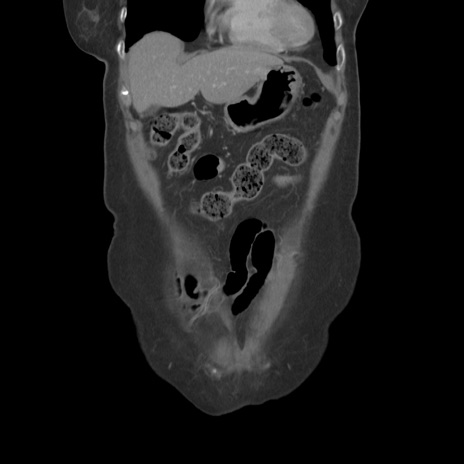

症例19(冠状断像)

【症例】80歳代女性

【主訴】下腹部痛

【現病歴】約8時間前より下腹部痛の出現あり、救急外来受診。

【既往歴】両側付属器切除

【身体所見】意識清明、下腹部正中に手術痕あり、その部位に一致して圧痛と反跳痛あり。腸蠕動音は亢進。

【データ】WBC 9300、CRP 0.15